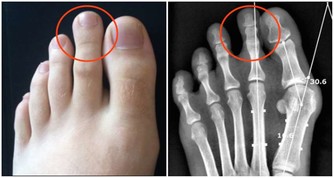

***4、下肢動脈硬化、閉塞***

患有心腦血管病、高血壓、高血脂、糖尿病者,當出現下肢酸痛、腿抽筋、行走不便等症狀時,應該想到是否有動脈硬化、狹窄或閉塞。